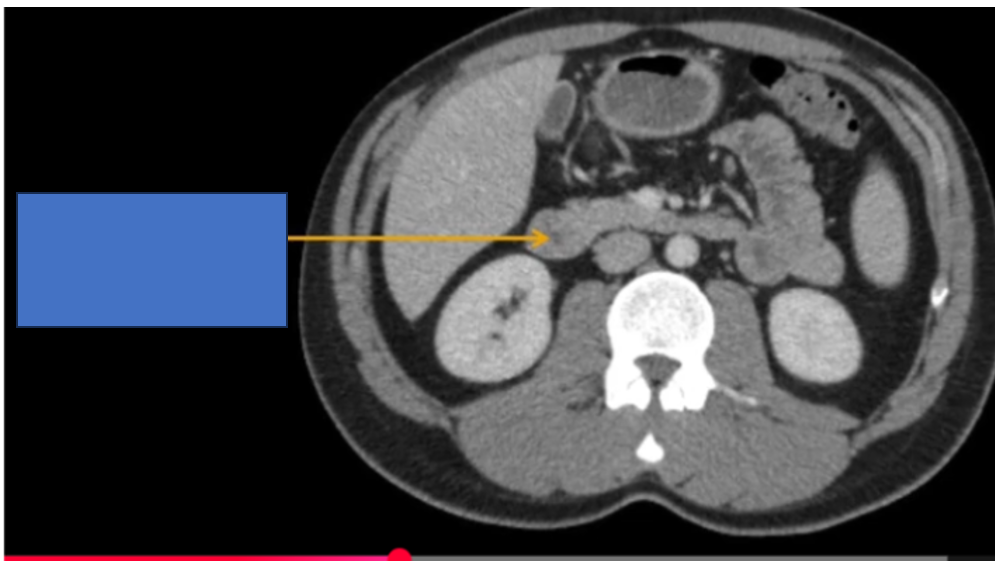

b) Niệu quản ở?